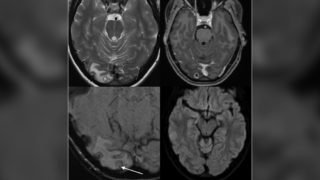

La risonanza magnetica mostra le cisti e le larve nel cervello della donna. Credit: The American Journal of Tropical Medicine and Hygiene / CNN

La donna accusava forti mal di testa due o tre volte al mese che curava con farmaci prescritti per l’emicrania. Tuttavia, il suo ultimo mal di testa è durato più di una settimana e si è manifestato con sintomi più gravi, incluso l’offuscamento della vista. Una risonanza magnetica del cervello ha portato i medici a credere che potesse essere un tumore la causa del suo dolore, ma dopo aver operato e rimosso la lesione, hanno scoperto che in realtà si trattava di una cisti piena di larve di tenia.

Questa condizione è nota come neurocisticercosi – l’infestazione del sistema nervoso centrale da parte degli stadi larvali, o cisticerchi, di Taenia solium –  che può causare sintomi neurologici quando si sviluppano cisti larvali nel cervello. Il parassita viene comunemente trasmesso consumando carne di maiale poco cotta o entrando in contatto con cibo, acqua e terreno contaminati da uova di tenia. La 25enne, che lavorava come barista, era considerata a rischio nullo o molto basso di infezione da larve di tenia, ma si ritiene che in qualche modo avesse ingerito accidentalmente uova di tenia. La migliore linea di difesa contro un’infezione simile è quella di cuocere la carne a temperature di sicurezza, lavarsi le mani con sapone prima dei pasti e mangiare solo cibo cucinato in condizioni igieniche.